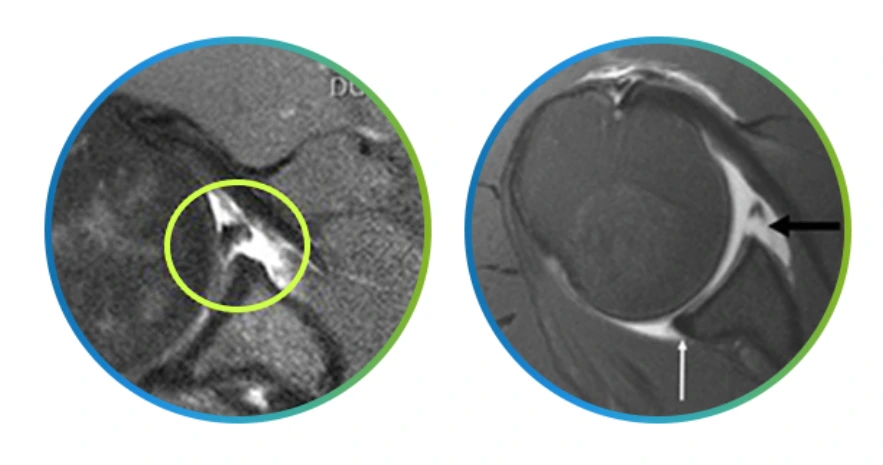

방카르트병변.PNG

방카르트 병변이 습관성어깨탈골을 일으키는 원인은 일단 상완골두가 앞으로 빠지면서 전발 관절와순이 손상되면 파열 부분이 완전히 회복되지 않으면서 작은 충격에도 어깨가 탈골될 수 있기 때문이에요.

힐삭스병변.PNG

방카르트 병변

전영식 원장님 “어깨탈골과 함께 관절와순 손상 가운데 상완골두가 앞으로 빠지면서 전방의 관절와순이 동시에 손상되는 질환이 방카르트 병변입니다. 이 방카르트 병변은 습관성어깨탈골과 같이 재발성 탈골원인의 97% 정도를 차지할 정도이지요”라고 습관성탈골의 대부분은 방카르트 병변이라고 알려주시네요.

힐삭스 병변

어깨관절의 탈구로 인해 어깨관절과 맞닿는 상완골두 부분에 골결손이 생기는 것이 힐삭스 병변인데요. 방카르트 병변과 마찬가지로 외상으로 인해 어깨탈골이 발생하고 제 자리를 찾아가는 과정이 반복되면서 발생하며 잦은 어깨관절의 탈골과 상완골두 부위의 통증이 나타납니다.